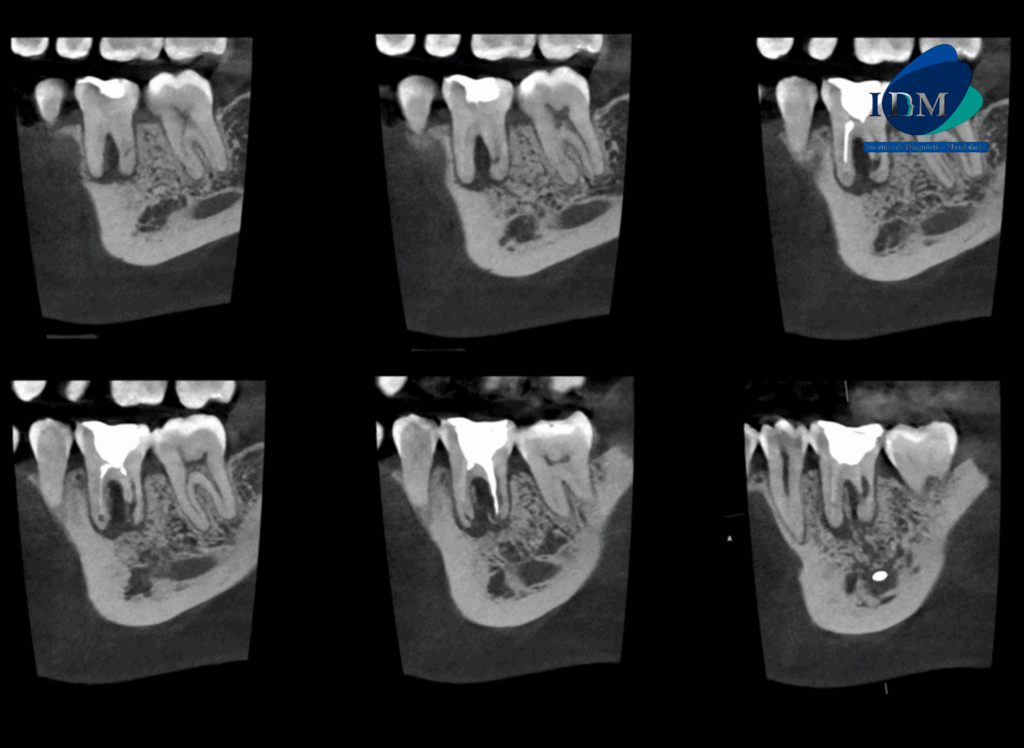

CORTES TANGENCIALES

CORTES TRANSAXIALES

A la evaluación de la tomografía computarizada se puede observar el tratamiento de conductos de ambas raíces, sim embargo el conducto distal presenta una obturación orientada hacia la superficie interna a nivel de tercio medio radicular (vista en cortes axiales), asimismo observamos en cortes tangenciales la reabsorción radicular externa de la raíz distal que compromete el tercio medio y apical. La raíz mesial presenta reabsorción radicular externa de tercio apical. Finalmente se evidencia compromiso de la tabla ósea lingual (cortes transaxiales) y osteítis condensante circundante.